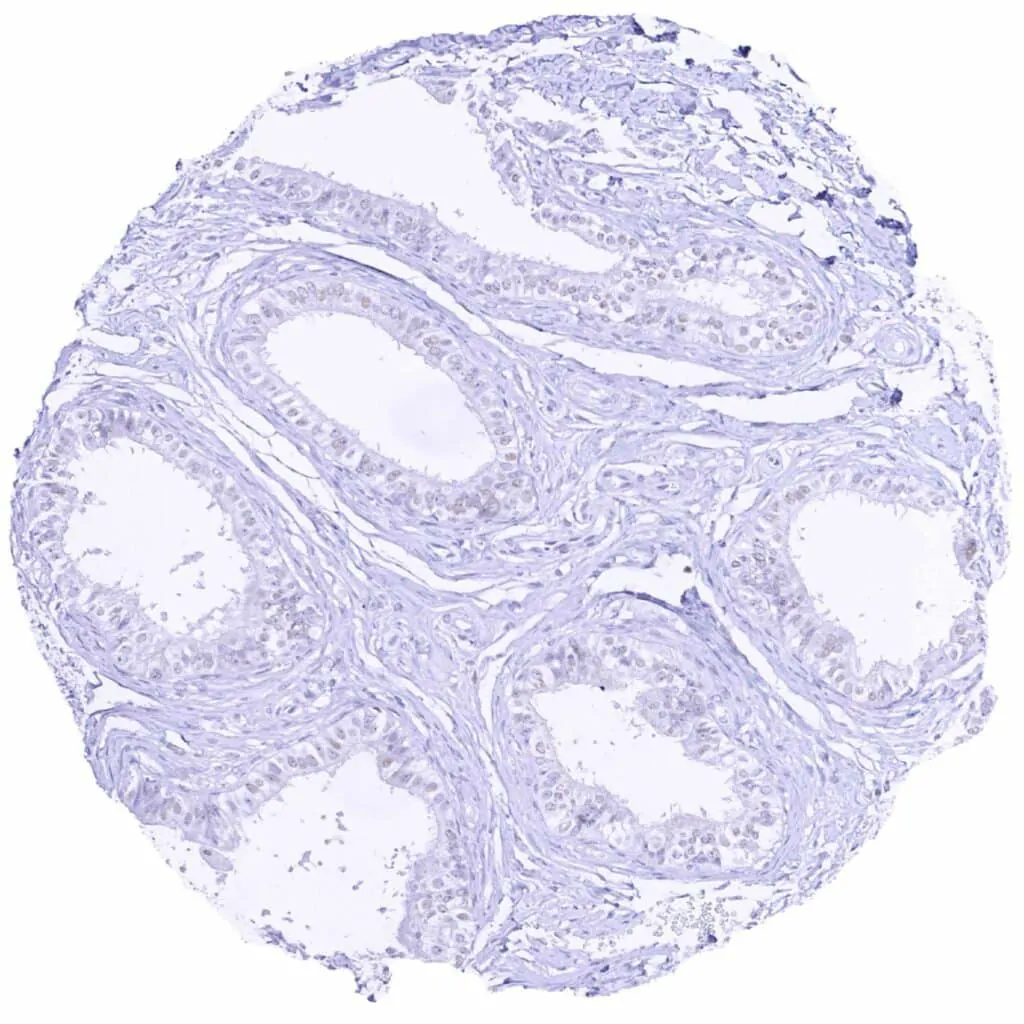

Epididymis (Caput)